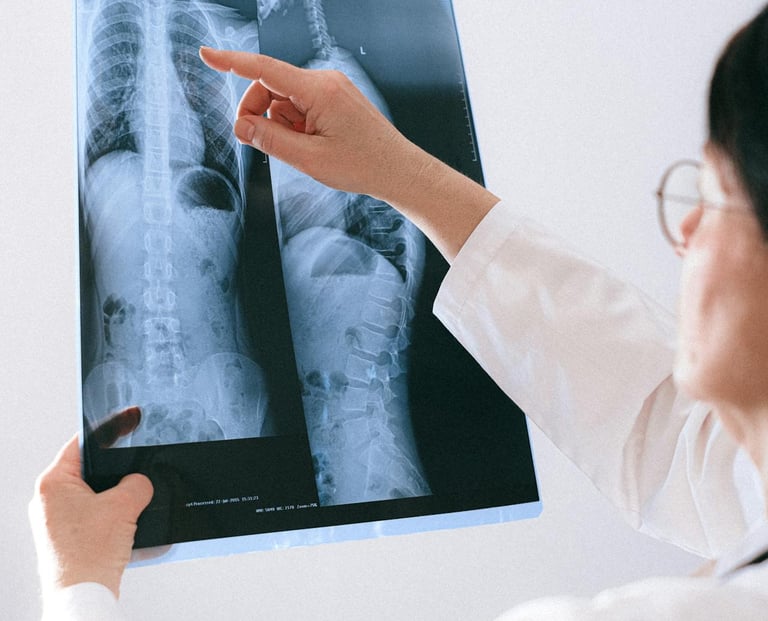

Les examens d’imagerie

Selon la situation, différents examens peuvent être prescrits :

Radiographie lombaire

Permet d’évaluer les structures osseuses et l’arthrose.